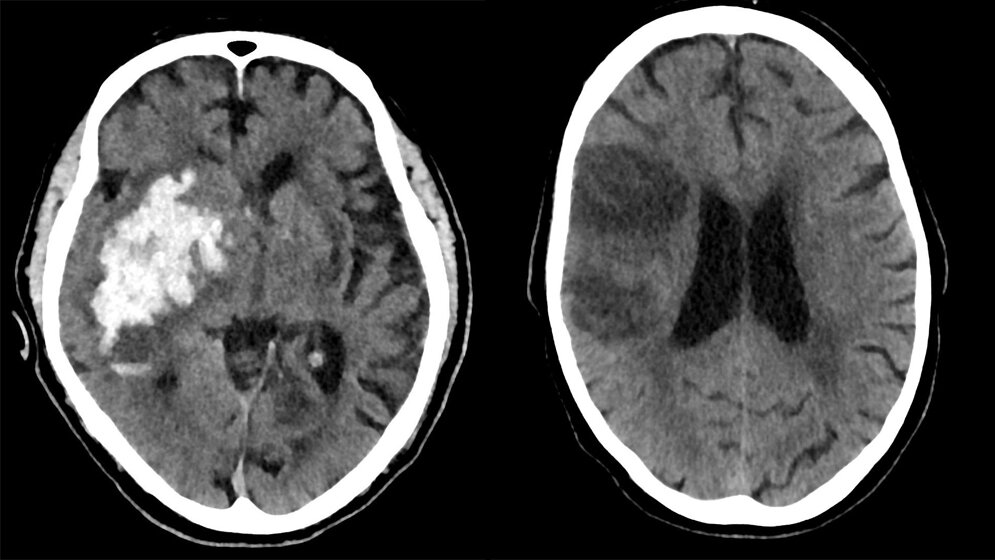

Gerade beim Verdacht auf einen Schlaganfall ist ein schnelles Handeln erforderlich. Eine schnelle Differenzierung, ob ein verschlossenes Blutgefäß oder eine Hirnblutung verantwortlich ist, ist essentiell. Zwar seien laut Glüer die Symptome in beiden Fällen ähnlich, die Konsequenzen unterscheiden sich aber. Liegt ein verschlossenes Blutgefäß vor, müssen spezielle Medikamente schnellstmöglich die Durchblutung des betroffenen Hirnareals wiederherstellen. Bei einer Hirnblutung muss diese gestoppt werden, sodass Schädigungen durch austretendes Blut bestmöglich vermieden werden.